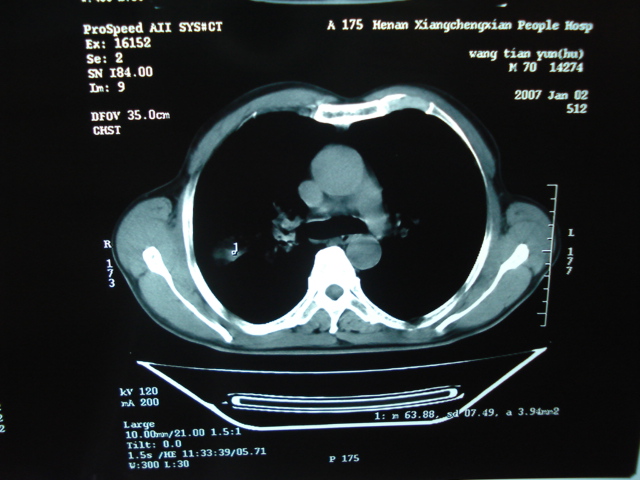

以下是引用狙击手在2007-4-18 20:17:00的发言:[br]原:2007/1/22号ct片:右肺上叶可见片状、云雾状高密度影,右肺上叶后段可见三角形高密度影,尖端指向肺门,右肺上叶后段支气管壁不规则增厚,管腔不规则增厚,纵隔未见肿大淋巴结.[br] 今ct:右肺上叶片状影增大,右肺上叶后段不张及右肺上叶后段支气管壁不规则增厚未见变化,右肺下叶背段支气管壁不规则增厚.[br] 如果考虑肺结核,但从临床证据看竟然没有一项支持肺结核,不知患者是否已经过正规抗结核治疗。没有的话,3个月了前后片看起来变化不大,似乎有不太符合肿瘤征象,不知患者是否抗炎治疗过,下叶支气管增粗还是要高度警惕,同意楼主意见,将常规病理,生化检查再做一遍。[br]

以下是引用狙击手在2007-4-18 20:17:00的发言:[br]原:2007/1/22号ct片:右肺上叶可见片状、云雾状高密度影,右肺上叶后段可见三角形高密度影,尖端指向肺门,右肺上叶后段支气管壁不规则增厚,管腔不规则增厚,纵隔未见肿大淋巴结.[br] 今ct:右肺上叶片状影增大,右肺上叶后段不张及右肺上叶后段支气管壁不规则增厚未见变化,右肺下叶背段支气管壁不规则增厚.[br] 如果考虑肺结核,但从临床证据看竟然没有一项支持肺结核,不知患者是否已经过正规抗结核治疗。没有的话,3个月了前后片看起来变化不大,似乎有不太符合肿瘤征象,不知患者是否抗炎治疗过,下叶支气管增粗还是要高度警惕,同意楼主意见,将常规病理,生化检查在做一遍。[br]